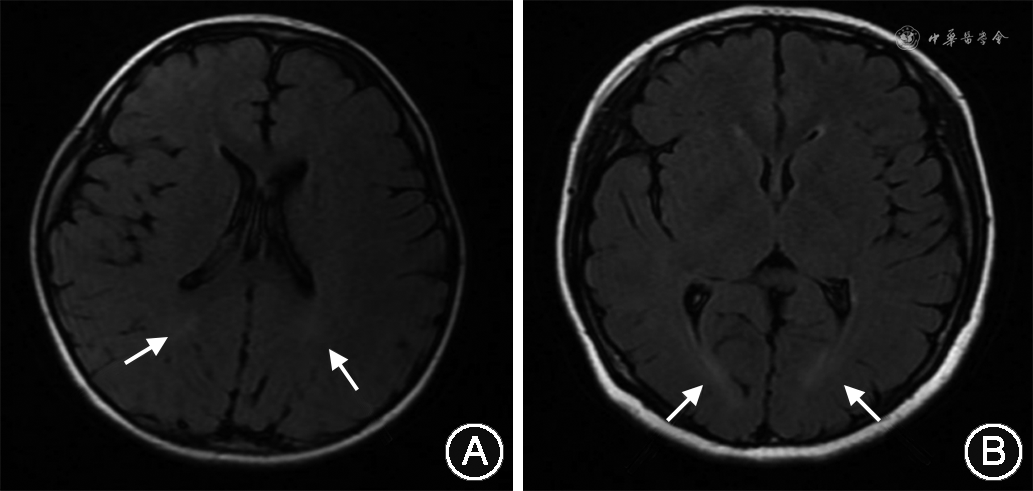

患儿 男,3岁3月龄,因“运动、语言发育落后1年余”于2020年3月至青岛大学附属医院儿童保健科门诊就诊,患儿就诊时仅会说“爸爸、妈妈、不要”等2字词语,表达意愿时仅会说“要”或手指示,情绪不稳定,容易发脾气,不会跳跃,自理能力欠佳。门诊行格塞尔发育量表示低于同龄正常幼儿,门诊考虑为“全面发育迟滞”。23月龄时无明显诱因出现抽搐1次,表现为双眼上视,口唇发绀,四肢抖动,呼之不应,无口吐白沫,无尿、粪失禁,持续1 min缓解。行颅脑磁共振成像(magnetic resonance imaging,MRI)未见异常,3 h视频脑电图未见异常,血常规、肝功能正常,血遗传代谢病氨基酸和酰基肉碱谱分析、尿液有机酸综合分析均未见明显异常。初步诊断为“癫痫”。给予丙戊酸钠3 次/d,4 mL/次,未再出现癫痫发作。患儿足月剖宫产出生,系其母第1胎第1产,出生时哭声响亮,Apgar评分不详,出生体重3 200 g。5月龄会抬头,6月龄会翻身,9月龄会坐,14月龄会爬,16月龄会走,2岁6月龄会喊爸妈。父亲(32岁)表型正常,母亲(30岁)有“癫痫”病史,1岁时出现痫性大发作,表现为双眼上翻,意识丧失,四肢抽搐,持续1~2 min缓解。服用丙戊酸钠250 mg,2 次/d控制效佳,服药5年后自行停药再次出现痫性发作,表现同前。口服“苯妥英钠50 mg,2次/d、卡马西平100 mg,2次/d”治疗,近2年无痫性发作。患儿母亲自幼智力障碍,未能上学。患儿母亲反应迟钝,记忆力差,Romberg征加强试验不稳,走直线不能。患儿母亲简易精神状态量表总分为9分,蒙特利尔认知评估量表总分为13分。心肌酶谱、肌电图、心脏超声均未见明显异常,颅脑MRI显示脑室周围白质异常信号(图1),脑电图未见异常。父母及外祖父母非近亲婚配。外祖父母和姨妈表型均正常。

辅助检查:婴儿—初中学生社会生活能力量表为9分;不同年龄阶段格塞尔发育量表结果均显示异常(13月龄大运动发育商68,细动作发育商68,应物能发育商68,言语能发育商60,应人能发育商64;23月龄大运动发育商86,细动作发育商74,应物能发育商69,言语能发育商48,应人能发育商63;3岁3月龄大运动发育商53,细动作发育商48,应物能发育商51,言语能发育商46,应人能发育商51)。心肌酶谱、肌电图、心脏超声均未见明显异常,颅脑磁共振成像显示脑室周围白质异常信号(图1),脑电图未见异常。